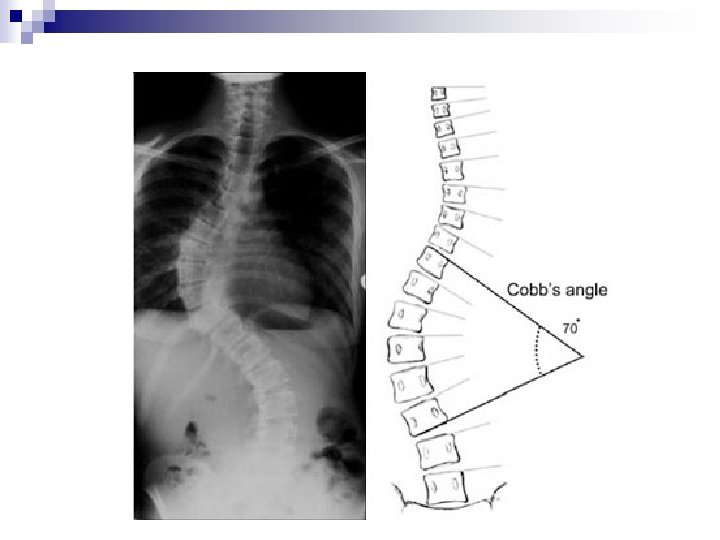

Radiographie (série scoliotique) Une scoliose est définie par ses limites (vertèbres les plus inclinées sur l’horizontale), son angle (mesuré en degrés selon la méthode de Cobb) et son côté. Le côté de la courbure est défini par le côté de la convexité : la radiographie se regarde comme si l’on voyait le patient de dos. En général, les scolioses sont : dorsale droite et lombaire gauche.

n n n La vertèbre sommet (VS) ou vertèbre apicale est la vertèbre horizontale qui, au sommet de la courbe, présente le maximum de rotation. Elle est celle dont le corps vertébral est le plus désaxé par rapport à l’axe occipital. La vertèbre limite est celle qui, à la limite supérieure (Vertèbre Limite Supérieure : VLS) ou inférieure (Vertèbre Limite Inférieure : VLI) d’une courbure, présente le maximum d’inclinaison par rapport à l’horizontale. Lorsqu’il existe deux courbures, la vertèbre limite à la jonction des deux courbures s’appelle la vertèbre transitionnelle. La vertèbre neutre est celle qui n’a pas de rotation : l’épineuse se projette sur l’axe médian du corps vertébral. Ces vertèbres neutres se trouvent dans le segment intermédiaire entre deux courbures ou entre une courbure et sa compensation

Angle de COBB